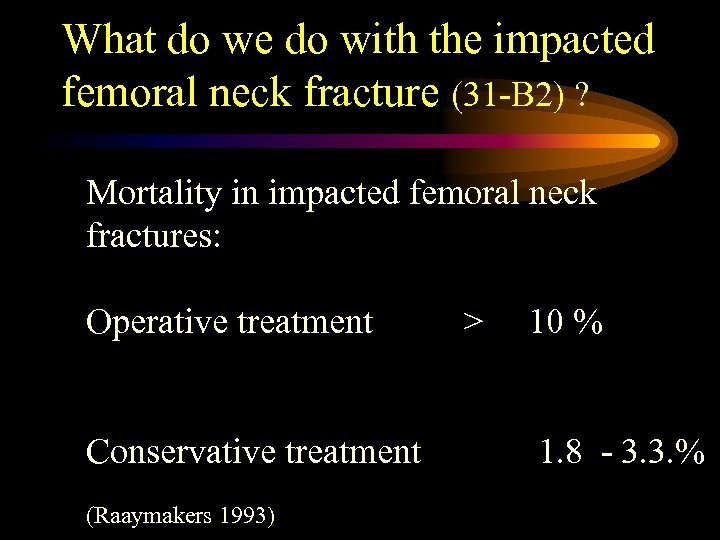

What do we do with the impacted femoral neck fracture (31 -B 2) ? Mortality in impacted femoral neck fractures: Operative treatment Conservative treatment (Raaymakers 1993) > 10 % 1. 8 - 3. 3. %

What do we do with the impacted femoral neck fracture (31 -B 2) ? Mortality in impacted femoral neck fractures: Operative treatment Conservative treatment (Raaymakers 1993) > 10 % 1. 8 - 3. 3. %